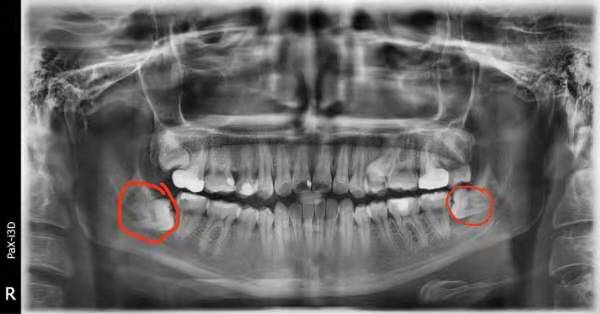

阻生智慧齒,如下圖:

在深圳維港歡樂口腔口腔掹此類智慧齒一颗一般需要15分鐘左右的時間。